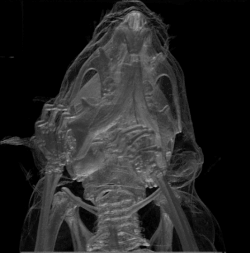

Corte transversal de una cabeza de caballo -